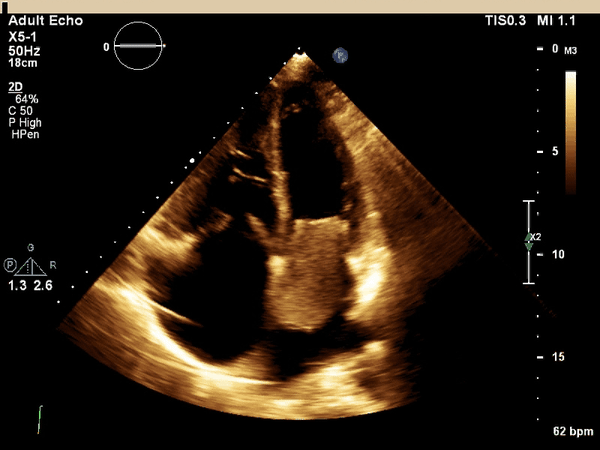

What cardiac condition is demonstrated in this image?

Rhabdomyosarcoma

LA thrombus

LA myxoma

Lipoma

Angiosarcoma